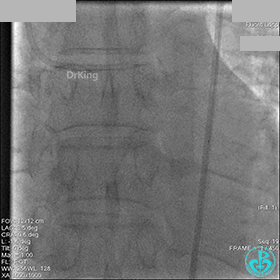

1周后再次上台,右冠脉3级血流,3段局限性严重狭窄,内膜模糊,应该是上次操作夹层遗留下的血肿。